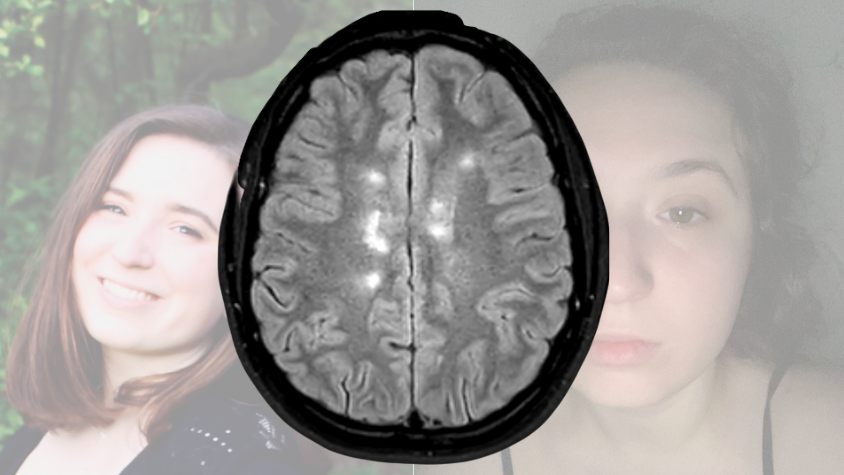

Auf der linken Seite ein ausgeblichenes Foto von der Protagonistin die lacht. Auf der rechten Seite eines, wo die Protagonistin müde und krank wirkt

Zwei verblasste Bilder der Autorin. In der Mitte ein MRT Bild mit aktiven Entzündungsherden im Hirn. | Quelle: Sarah Dodds

„Auf deinen MRT-Bildern sind weiße Flecken im Hirn und Rückenmark zu sehen“, erklärt mir die Ärztin. Besorgt schaut sie mich an, als sollte ich wissen, was das jetzt für mich bedeutet. „Um sicherzugehen, dass es sich um Multiple Sklerose handelt, muss Nervenwasser entnommen werden“, sagt sie und greift nach der viel zu langen Nadel.

MRT Bilder

MRT Aufnahme vom Hirn mit aktiven Entzündungsherden.